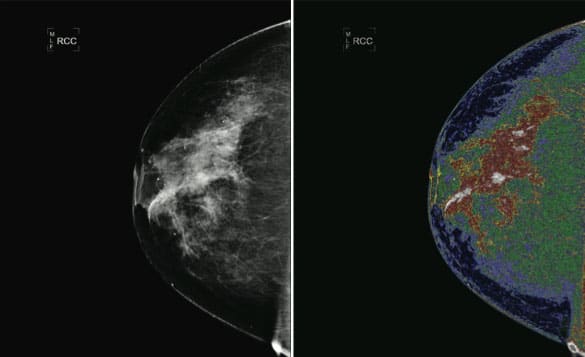

“Trained professionals can use the MED-SEG system to separate two-dimensional images into digitally related sections or regions that, after colorization, can be individually labeled by the user,” explained Fitz Walker, president and CEO of Bartron Medical Imaging.

In July 2010, the MED-SEG system received FDA 510(k) clearance to be used by trained professionals — physicians, radiologists, nurses, and medical technicians — to process images. The MED-SEG can be used to process images from various sources such as MRIs, CT scans, X-rays, ultrasounds, and mammograms. These images can be used in radiologists’ reports and communications, but the processed images should not be used for primary image diagnosis.

“One problem with mammograms is they often give a false negative for detecting abnormalities in women’s breasts. Women who either have high breast density or a strong family history of breast cancer are often sent for MRIs, which are costly, very uncomfortable, and have a high false positive rate resulting in many unnecessary biopsies. Neither imaging modality can detect cancers without a significant number of inaccuracies either missing cancer or overcalling cancer,” said Brewer. “In addition, reading these tests relies on detecting differences in density, which is highly subjective. The MED-SEG processes the image, allowing a doctor to see a lot more detail in a more quantitative way. This new software could save patients a lot of money by reducing the number of costly and unnecessary tests.”

Since radiologists use personal judgment to look for differences in density when they read a mammogram, CT scan, or MRI, this process may be subject to human error. Dr. Brewer hopes to use results from the clinical trials to develop an algorithm that can more objectively distinguish cancerous mammogram results from noncancerous results.